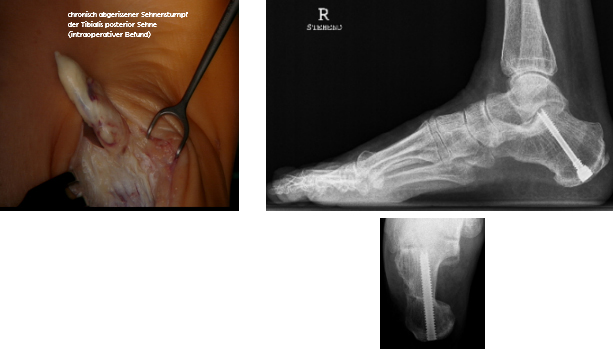

Bei der Operation muß die überdehnte und damit nicht mehr funktionstüchtige und manchmal chronisch abgerissene hintere Schienbeinsehne (M. tibialis posterior) ersetzt und zusätzlich durch eine Durchtrennung und Versetzung des Fersenbeines unterstützt werden. Mit einer anschließenden 4-6 wöchigen Gipsbehandlung und folgender Geh-Schienenversorgung von ca 3 Monaten ist davon auszugehen, daß der Erkrankungsverlauf komplett gestoppt werden kann.